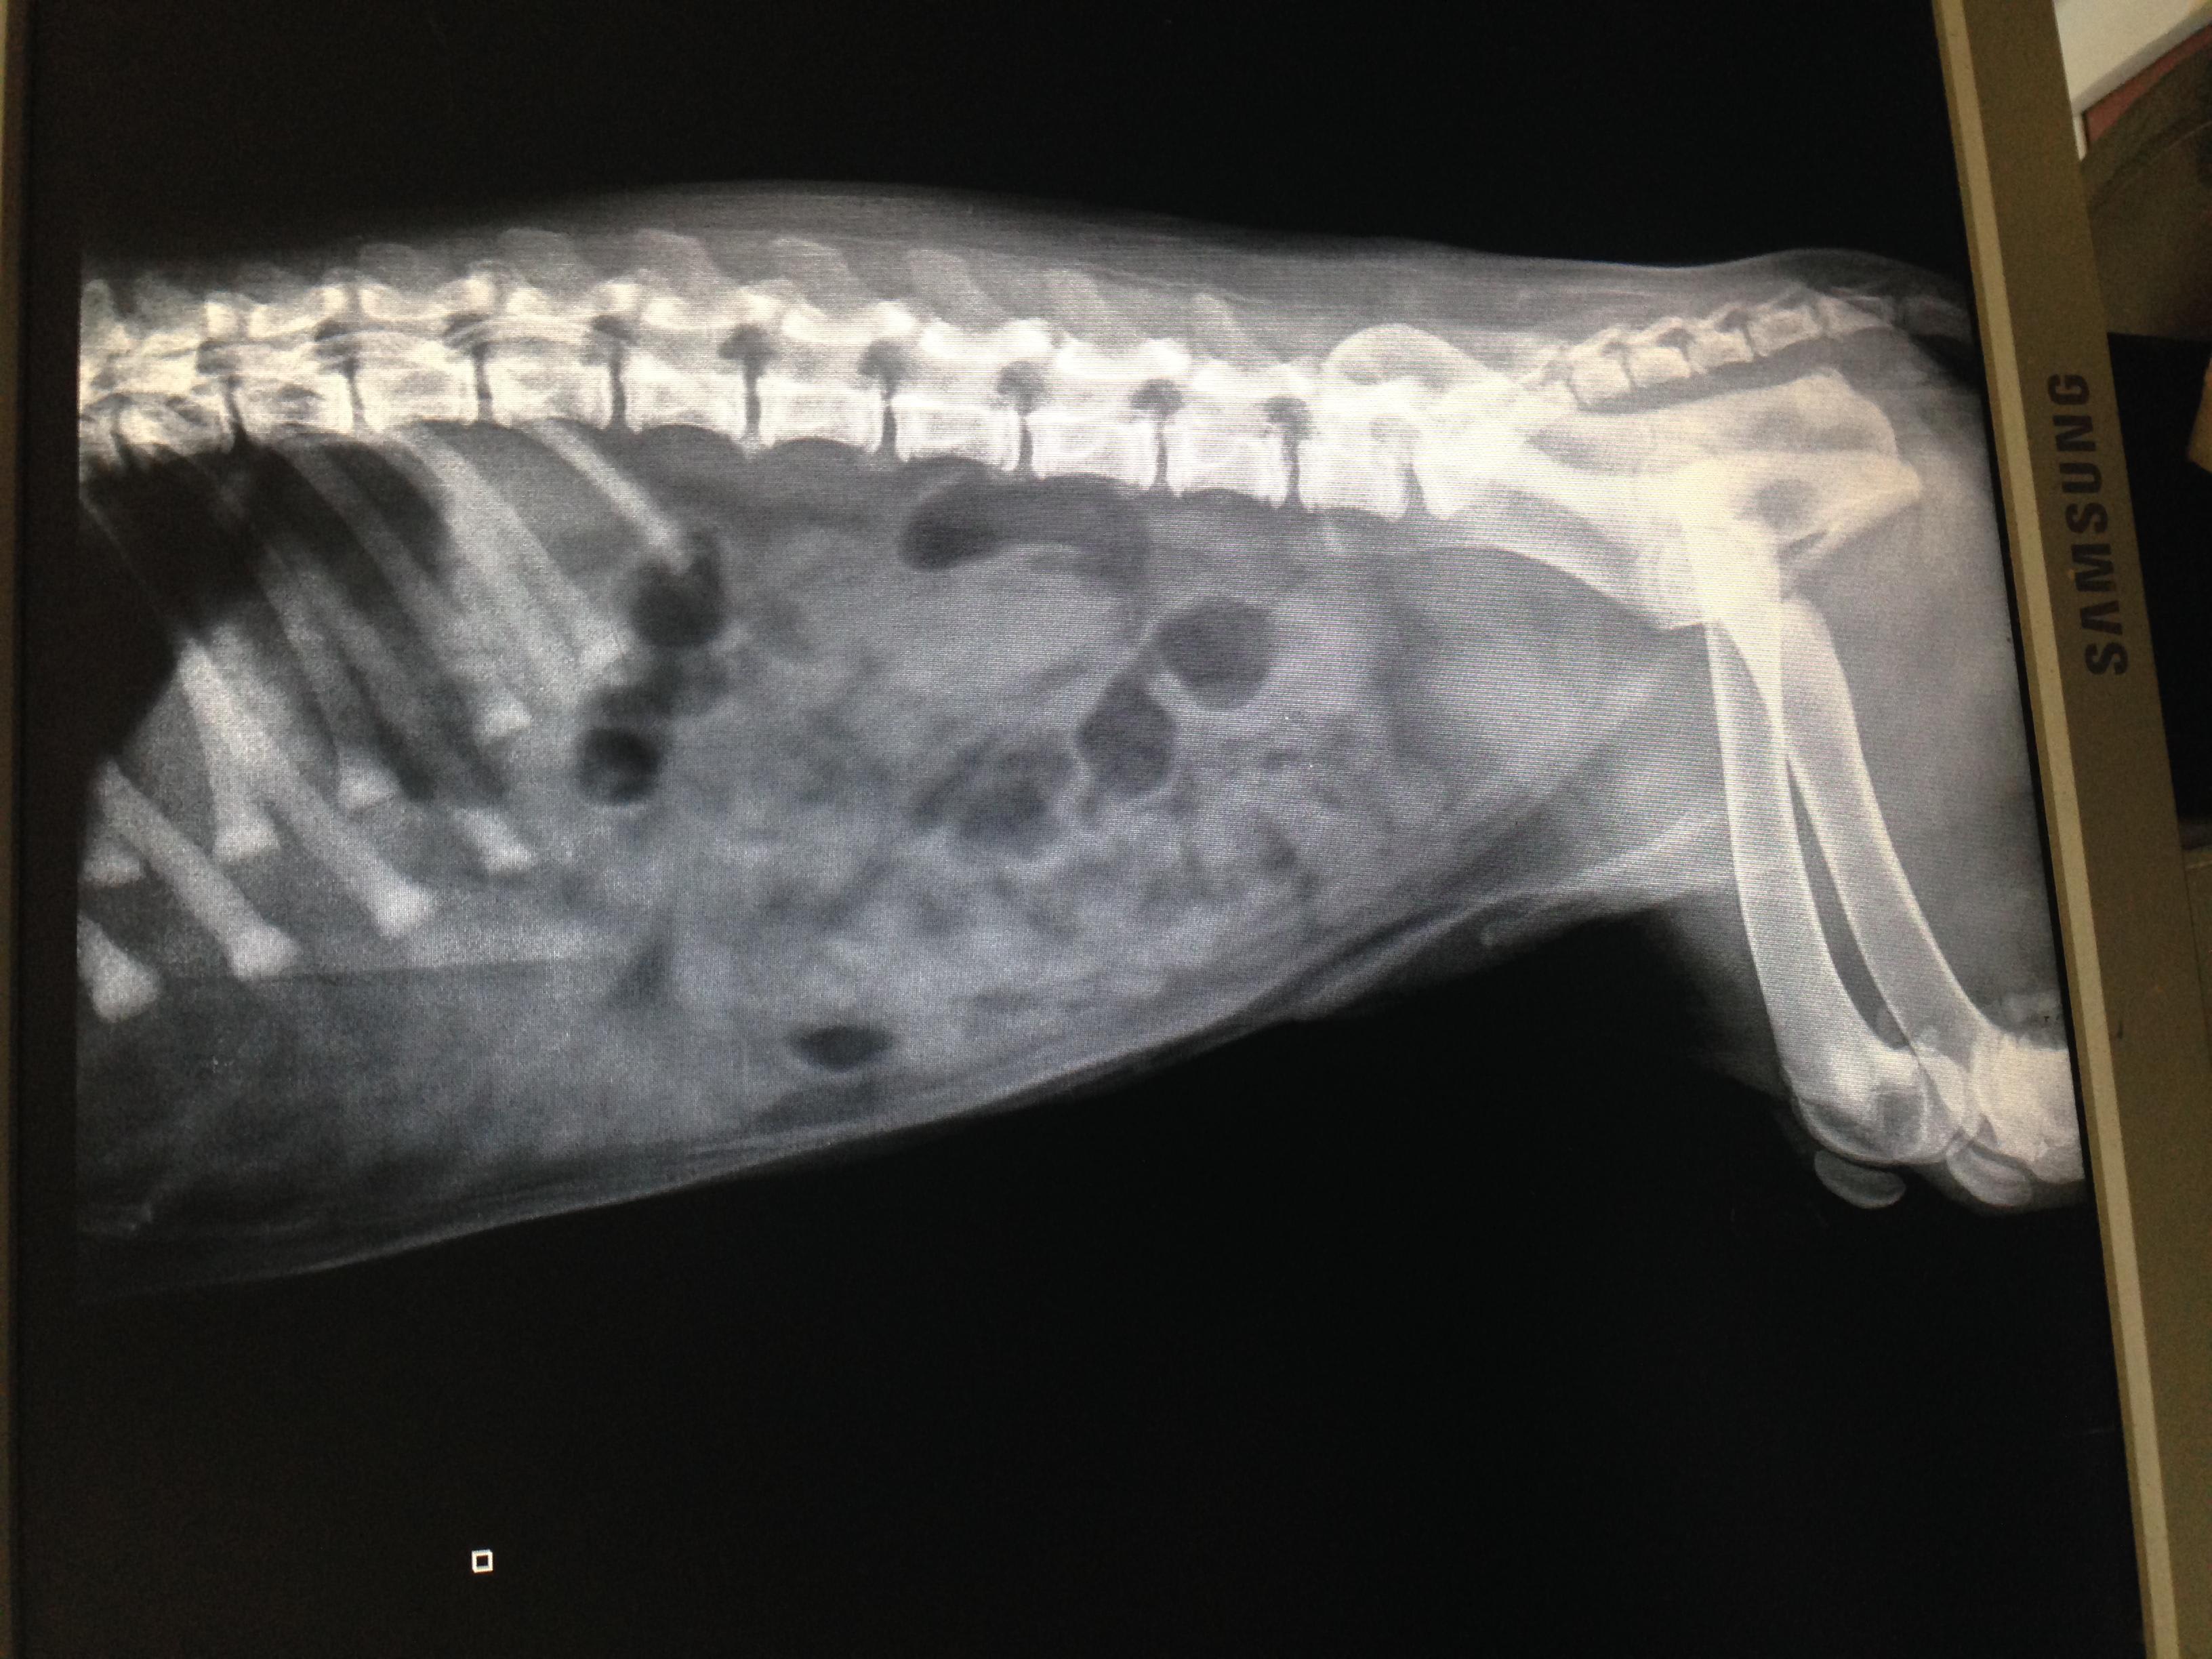

Common causes of bloody vomiting or diarrhea in a puppy include dietary intolerance, dietary indiscretion, intestinal parasites, GI blockage, toxic exposure, gastroenteritis, bacterial or viral (like parvo or distemper) infection, among others. The x-rays you provided are not diagnostic for any specific disease, but there are a couple large pockets of gas that could indicated GI blockage or a decrease in movement of the intestines, called ileus, Other diagnostics that can be performed are CBC, chemistry, parvo test, intestinal parasite screen, or coagulation profile. If you have additional diagnostic results, you can choose a one-on-one consult and we can discuss them fully and help you decide what else can be discussed with your vet.